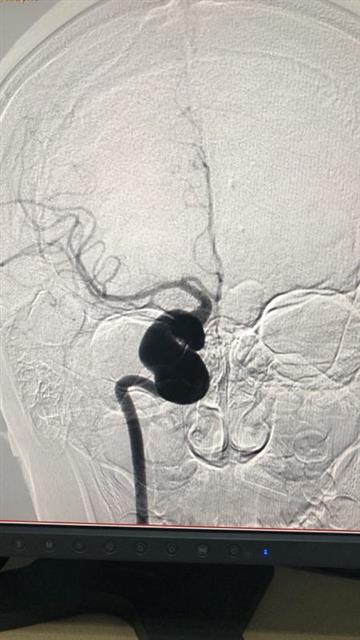

1月10日,同济医院神经外科牛洪泉教授见到了小锦,一看片子:脑内巨大动脉瘤!

“动脉瘤已开始产生明显的压迫症状,不治疗的话,不仅小锦的眼睛无法恢复,如果动脉瘤破裂出血风险更大,患者又如此年轻,必须救!”于教授说,超超过25毫米的脑动脉瘤被称为巨大动脉瘤,对其它专科或许只是个小病变,但脑血管比较细,超过10毫米的动脉瘤就比较大了。而且小锦的这个动脉瘤位于靠近脑袋正中的海绵窦内,周围神经、血管丰富,一旦处理不当,极可能影响正常的神经功能。

于教授说,小锦右眼睁不开、头痛,就是脑动脉瘤急速膨胀造成的。他在科内同陈坚、陈旭、曾令成等专家讨论了小锦的病情。动脉瘤靠近脑中心,位于右侧大脑最主要的动脉通道上,如一枚“巨大地雷”。其周围有众多重要的神经、血管。讨论了多种方案,先后排除保守治疗、直接开颅夹闭动脉瘤、介入治疗等治疗方式后,专家们决定:只有采取搭桥手术,修一条“栈道”,重建大脑血流通路,然后在动脉瘤两端堵住病变血管,孤立“地雷”。但这种手术难度极大,尤其在这么小年纪的病人身上实施。

手术从上午9时持续到下午5时,医生们顺利取出小锦左臂上10多厘米长的桡动脉,暴露右侧颈动脉以及开颅,并在荧光显微镜下,顺利完成了搭桥手术,最终成功孤立了危险的“地雷”。